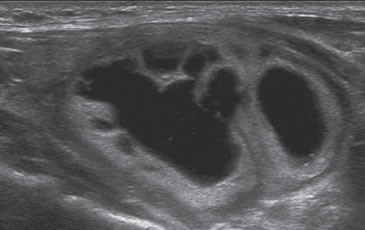

Los nódulos tiroideos pueden ser quísticos, sólidos o mixtos. Dentro de los mixtos pueden ser predominantemente quísticos (mayor de 50%) o predominantemente sólidos.

Un nódulo que tiene un componente quístico significativo, usualmente es un nódulo benigno hiperplástico, que ha acumulado abundante coloide (Figura 2a) o bien, un nódulo sólido que ha experimentado un proceso de degeneración colicuativa o hemorragia (Figura 2b). El coloide o el contenido líquido de un nódulo se ve anecogénico (negro en la imagen ecográfica) y las estructuras sólidas se ven ecogénicas (distintos tonos de grises), siendo la ecogenicidad similar al del parénquima tiroideo. En un nódulo sólido la ecoestructura y la ecogenicidad pueden ser variables. En general, la frecuencia de carcinoma es muy baja en nódulos quísticos13 y la mayoría de los carcinomas se presentan como nódulos sólidos (Figura 2c).

Figura 2. a) Quiste coloideo anecogénico y focos ecogénicos (flecha) con artefacto en cola de cometa; b) Nódulo mixto sólido-quístico (cabezas de flechas). Imagen vegetante (flecha) adherida a un tabique que se proyecta al lumen; c) Comparación entre el aspecto ecográfico de un cáncer papilar sólido (flecha abierta) y un quiste coloideo anecogénico.